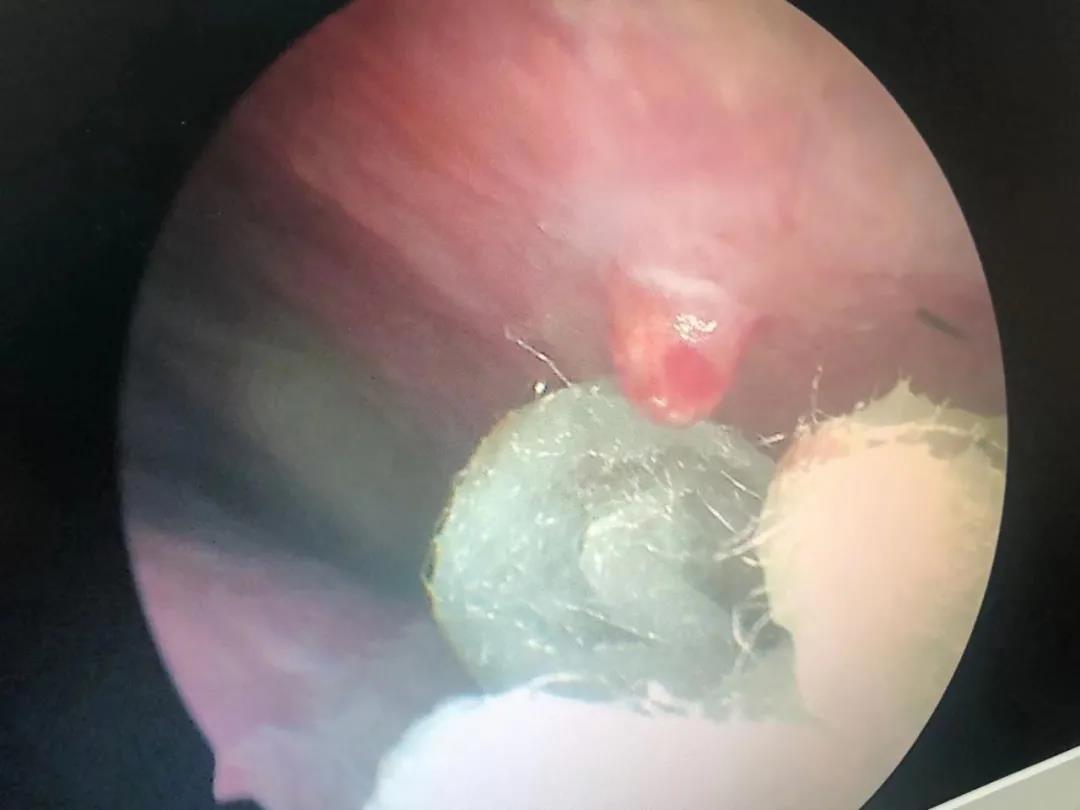

“你这个不是鼻中隔偏曲啊,是血管瘤造成的,你看这里有一个血管瘤”。耳鼻喉科专家黄定强博士通过鼻内镜检查发现,吴大叔鼻腔内有一颗约黄豆大小的血管瘤。

(吴大叔鼻内镜下血管瘤)

像吴大叔的情况,就是非常明确的鼻部毛细血管瘤。之后黄博士为吴大叔进行了局麻下鼻腔毛细血管瘤切除术。